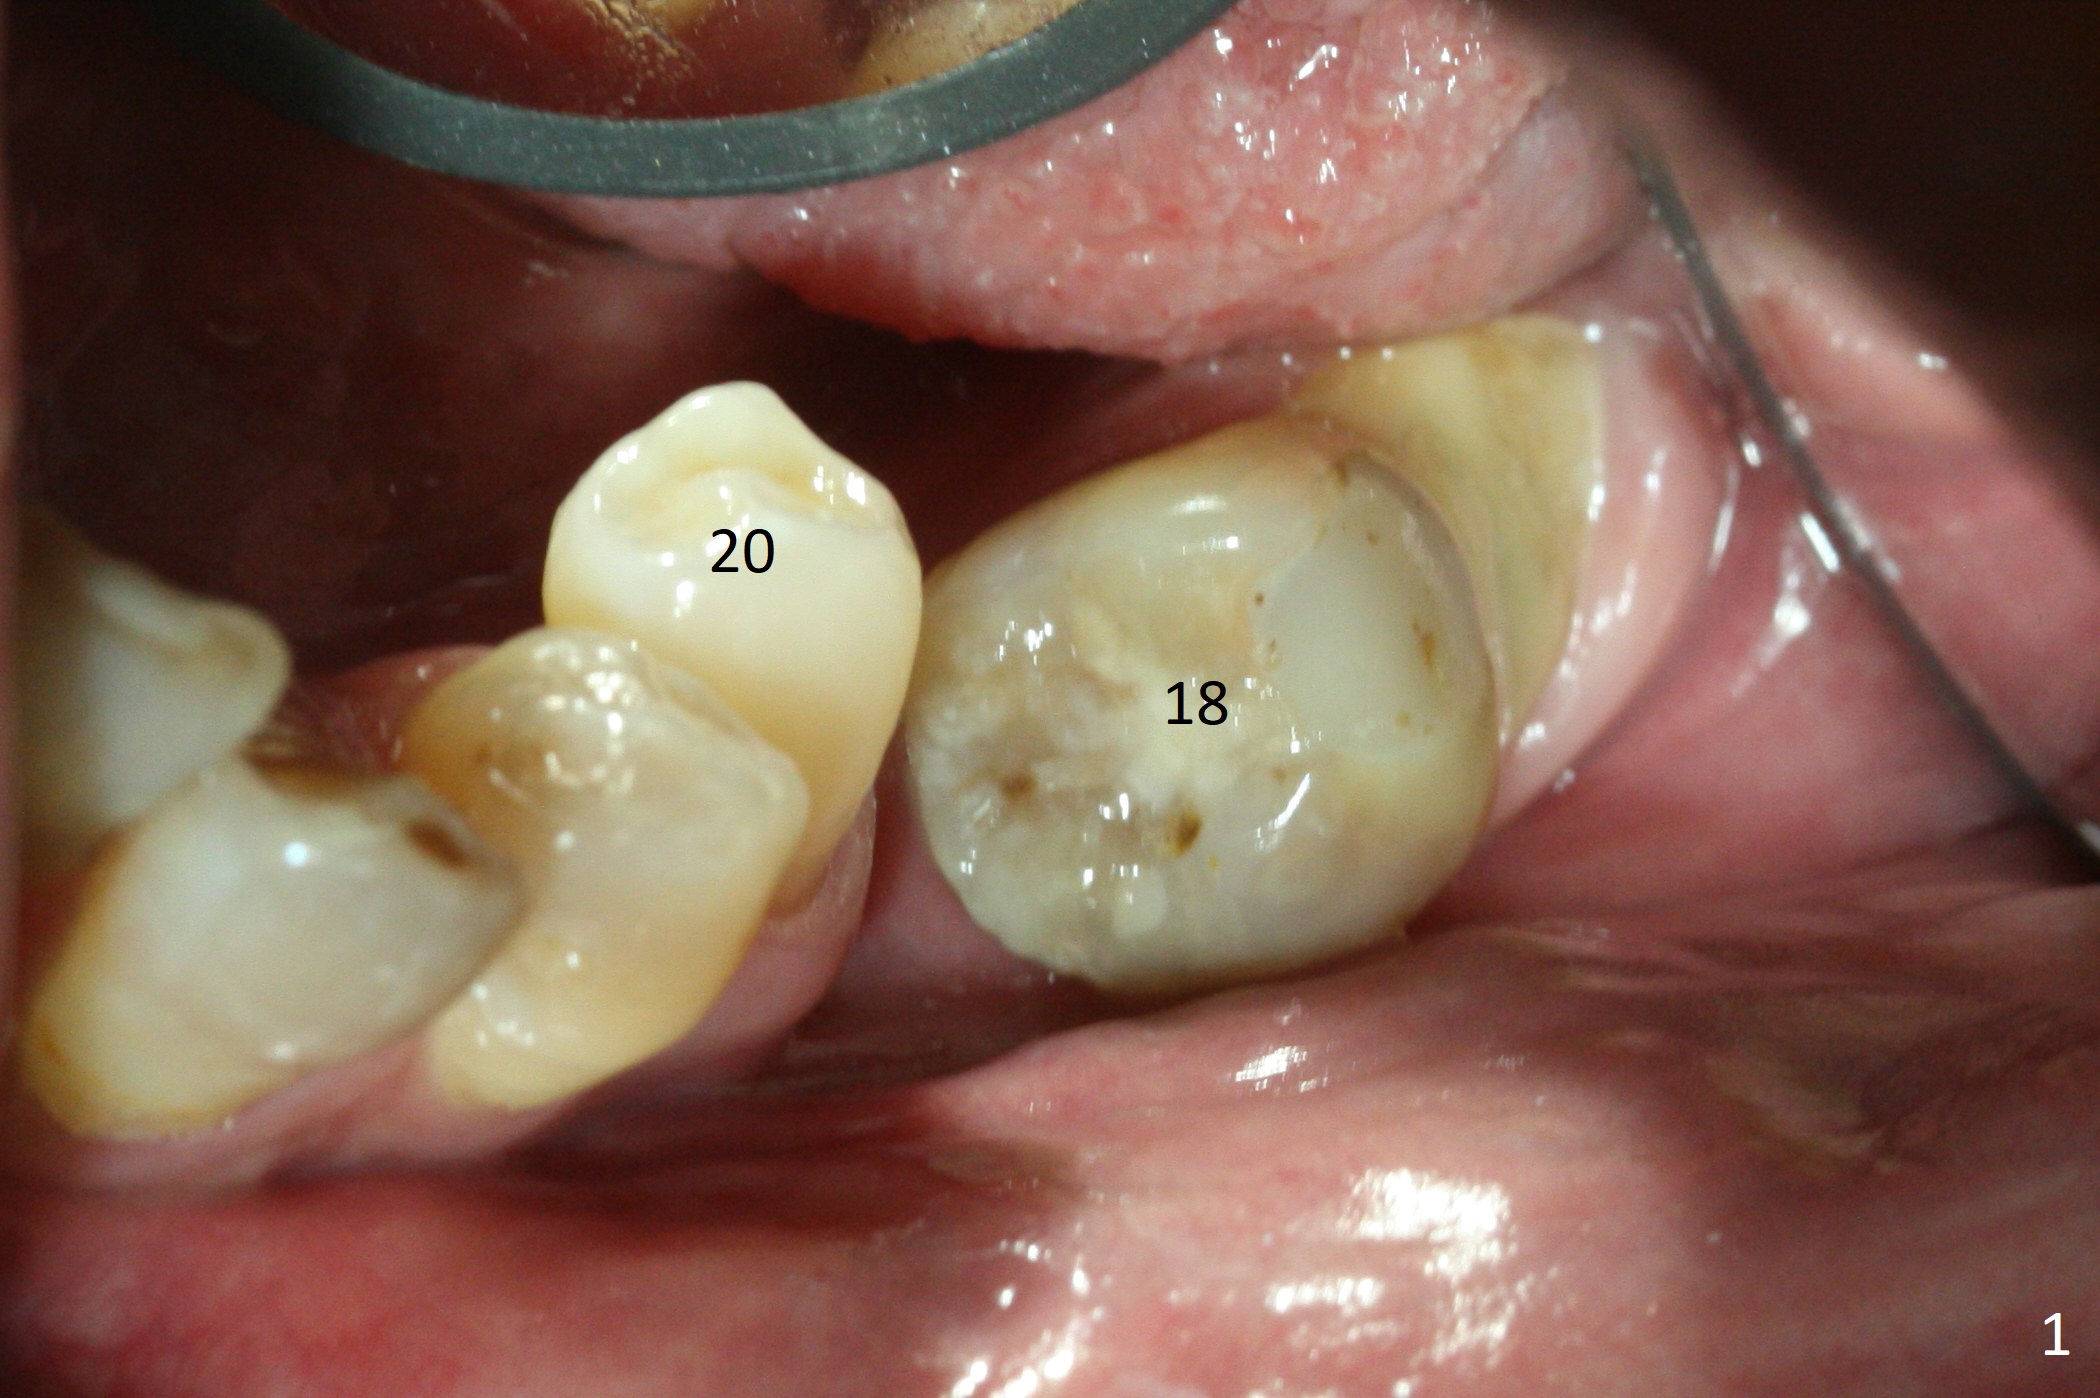

Preop photo shows severe mesial tilt of the tooth #18 (Fig.1). After extraction, the osteotomy is established in the apical end of the socket, where the buccolingual width is limited. It appears that an extra wide implant (5.9 mm) may perforate one of buccolingual plates. On the other hand, the buccal plate (Fig.2 double arrows) is intact and approximately 2 mm tall, whereas the lingual one is thin and lower. Initial osteotomy confirms that bone heights at #18 and 19 are 6 and 8 mm, respectively. Counting 2 mm of the buccal plate and bone graft lingually, a 8 mm long implant may be a practical option at the site of #18. After initial placement of two of 5x8 mm SM implants (Fig.3), the depth of the implant at #19 is adjusted twice (Fig.4,5). With placement of autogenous and allograft (Vanilla, Fig.5 *)) and abutments, a piece of cotton pellet is placed in each abutment well (access, Fig.6 *). Periodontal dressing is applied to the abutment wells for additional retention (Fig.7 *). Due to local poor oral hygiene, splinted provisional is fabricated 4 months postop (Fig.8) in preparation for limited orthodontic uprighting the tooth #20. The patient has pain with mastication at #18 eleven months post cementation (Fig.9). It appears that both of the implants should be removed with immediate replacement and bone graft. Prepare 4 PRF and sticky bone. The new implant will be 5.0 or 5.5x5 mm (Fig.10 green) with 2.3 mm platform (white). A block graft will be harvested from the ipsilateral ramus using 9/8 and 6/5 mm trephine burs for 2-3 mm in depth (Fig.11 blue). The ring graft will be seated around the platform over the implant (Fig.12).